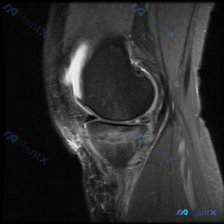

刚看到这个膝关节MRI读片的病例,有点典型,整理出来和大家分享一下思路。 病例基础信息 这是一份膝关节矢状位MRI影像,序列为T2WI或PDWI-FS,对软组织、水肿、韧带病变显示清晰。 影像学核心发现 1. 骨骼与关节软骨:髌骨后方关节软骨面不平整,髌骨软骨下骨可见片状高信号影,提示骨髓水肿或软骨...